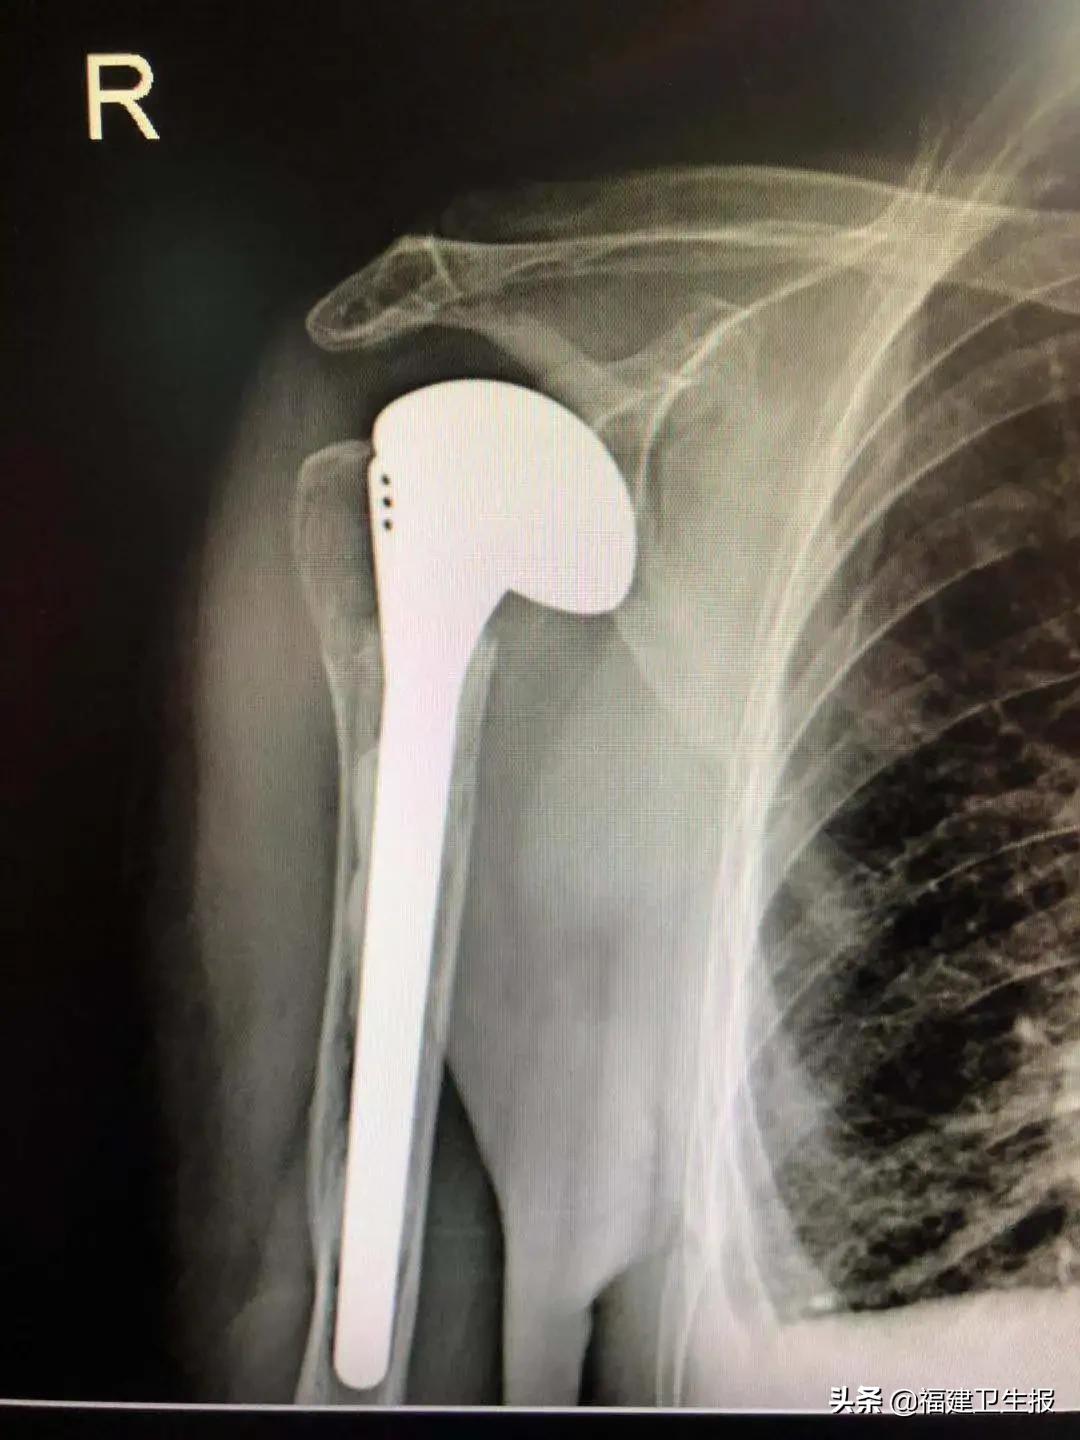

施行了肩关节人工肱骨头置换术

李坚主任立即制定了治疗方案,并请康复医院内科、麻醉科、重症监护室等多学科专家会诊和术前评估。11月2日,李坚主任团队仅仅花了40分钟,便顺利为黄奶奶完成了“右侧肩关节人工肱骨头置换术”,刀口仅约7厘米。

术后

术后第二天,黄奶奶已经可以正常活动右侧肩关节了,即将出院。